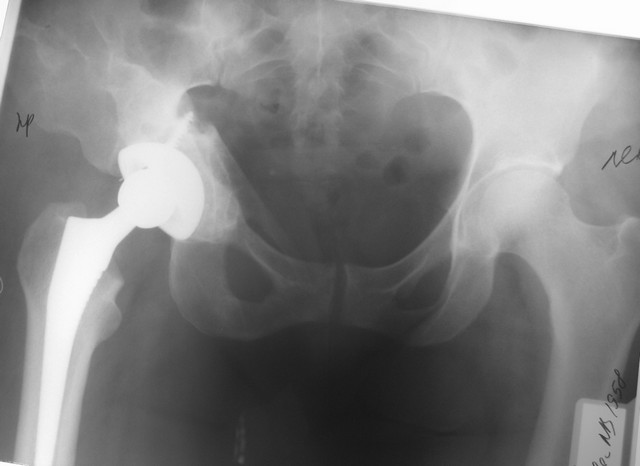

таз оказался стабильным, Corail-Duraloc, с пластикой дна.